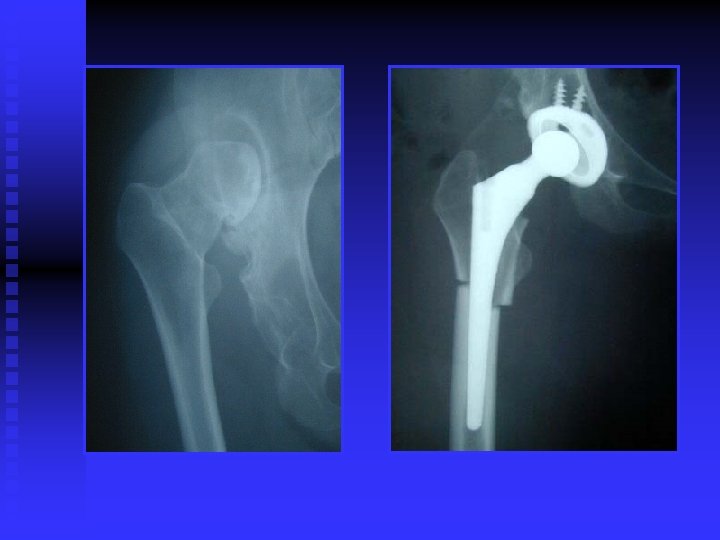

OA RÖNTGEN BULGULARI n Eklem aralığında daralma (kıkırdak incelmiş) n Eklem aralığının kalmaması (kıkırdak bitmiş) n Yük binen yerlerde kistler n Yük binmeyen yerlerde osteofitler

CERRAHİ TEDAVİ Artrodez (eklemin dondurulması) n Osteotomi (aks veya eklem uyumu düzeltilir) n Debridman (artroskopik temizleme) n Artroplasti n • • Parsiyel veya total protez Rezeksiyon (kısa ve fonksiyonu kötü ekstremite)